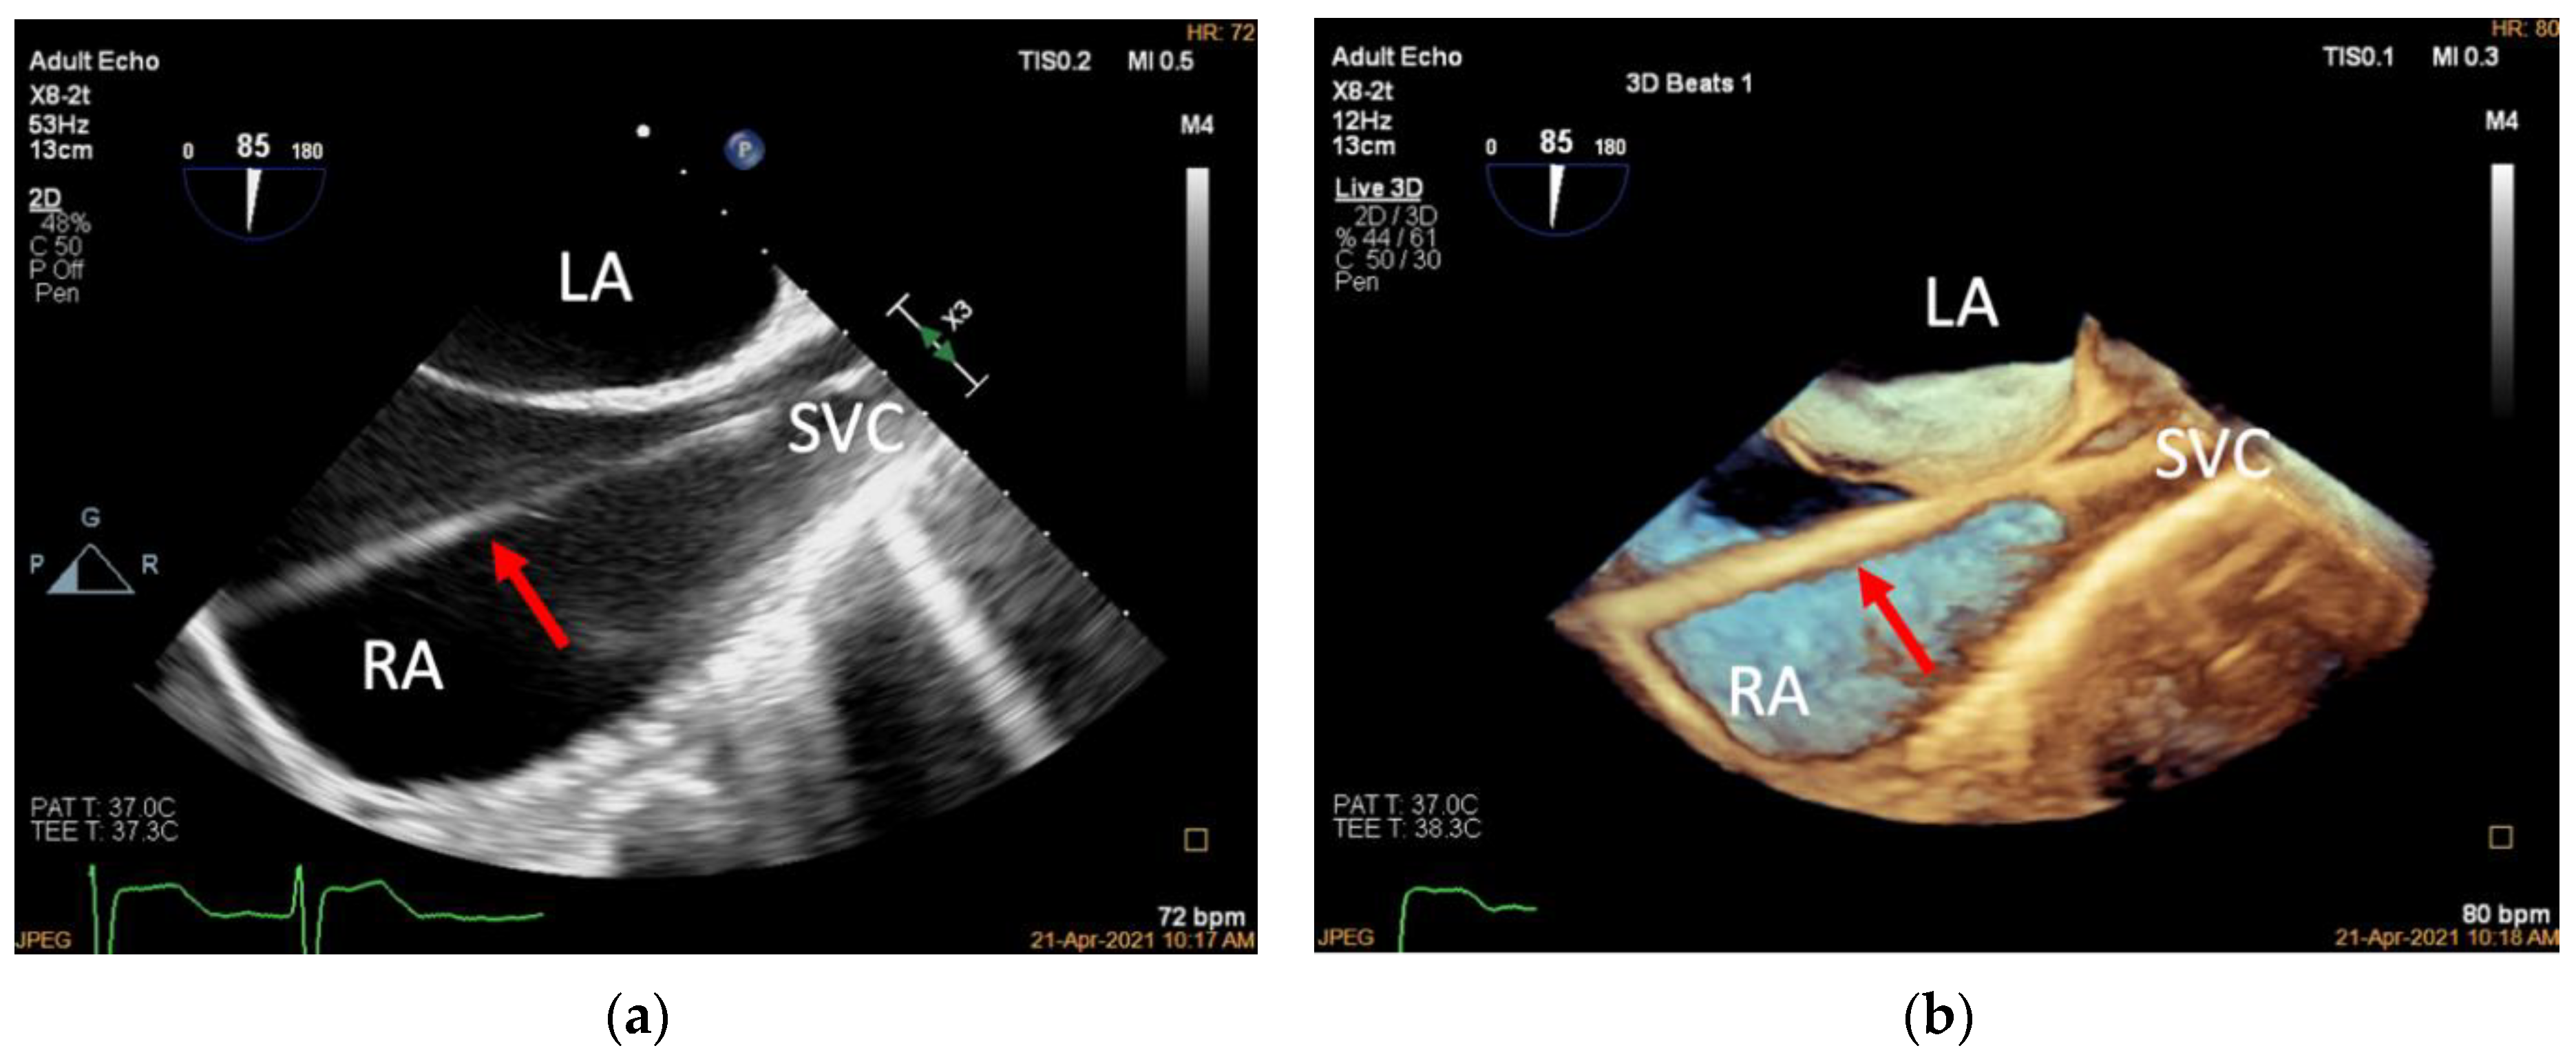

3.2. Introducing the Delivery System (Mid-Esophageal Bicaval View)

| Step 1. Introducing the delivery system | 2D and 3D mid-esophageal bicaval view | 70–110° | |

| 3D adjusted mid-esophageal bicaval view | 70–110° | Slight clockwise/counter-clockwise rotation of the probe from the mid-esophageal bicaval view for appropriate depth to visualize the TA | |